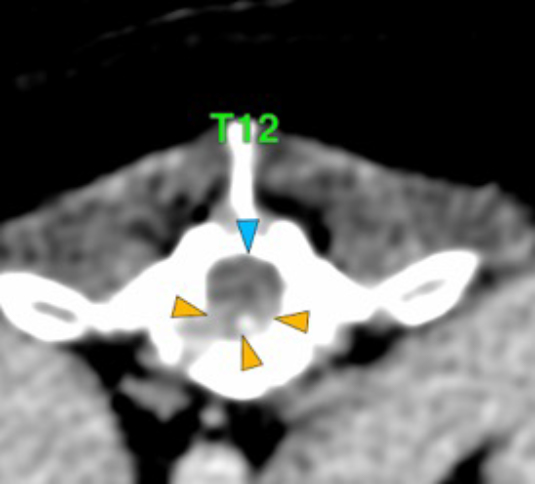

The osteolytic lesions have soft tissue attenuation that shows moderate and slightly heterogeneous post-contrast enhancement. In some of the vertebrae, the lesions cause lysis of the cortex and extend into the vertebral canal (orange arrows) causing variable degree of compression of the spinal cord and cauda equina (blue arrows). At the level of the vertebral bodies of T7, T8, T9 and T12 the lesions extend into the ventral and central aspect of the vertebral canal causing a mild compression of the spinal cord. At the level of T13, L1, L4 and L5 the lesions extend into the ventral and central aspect of the vertebral canal, causing moderate compression of the spinal cord. At the vertebral body of L6 the lesion extends into the ventral and central aspect of the vertebral canal, at the mid-aspect of L6, occupying approx. 90% of the diameter of the vertebral canal causing a severe compression of the cauda equina. At the level of L7, the lesion extends into the ventral and both lateral aspects of the vertebral canal, causing severe compression of the cauda equina.